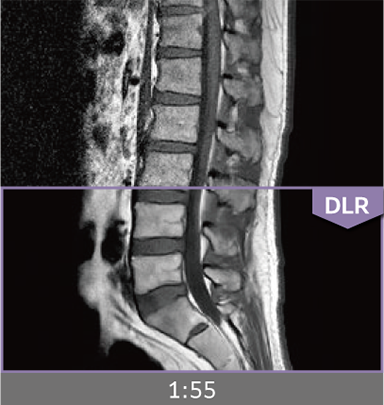

Combining high-speed imaging technology with Deep Learning reconstruction technology*3, Advanced Reconstruction with Deep Learning Synergy DLR, enables shorter exams and reduces image noise.

Images can be obtained at high speed by combining two proprietary technologies: IP-RAPID, which reduces imaging time while maintaining image quality, and Synergy DLR, which uses deep learning technology*6 to improve image quality

Under-sampling reduces imaging time, and iterative reconstruction with IP-RAPID reduces noise and artifacts.

In addition, Synergy DLR, an image reconstruction technology utilizing deep learning technology, further eliminates noise and produces images that are easier to use in making a diagnosis.